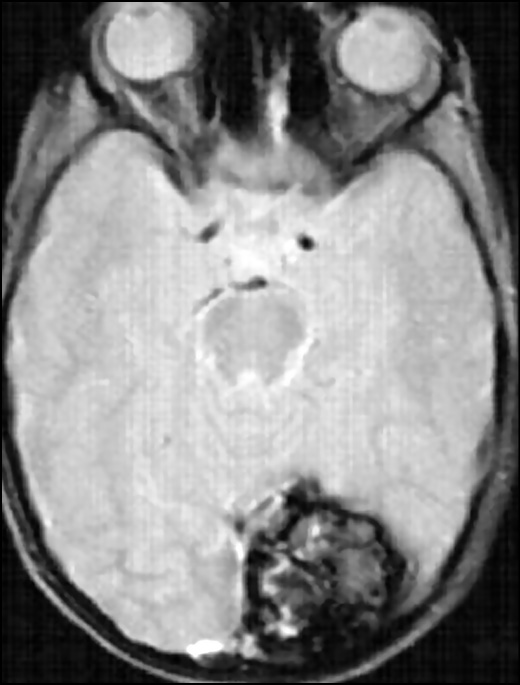

Hemosiderin deposits in and around the CM are considered a typical sign of repeated subclinical hemorrhages or erythrocyte lysis; they provide magnetic susceptibility to this pathological lesion, especially at a high-magnetic-field strength. The heterogeneity of the magnetic field in the presence of hemosiderin also contributes to the differentiation of blood flow and the effects of hemosiderin in CMs (Fig. 2) [16, 17].

Fig. 2. MR images of the brain in the axial view in the T1–WI (a, c), T2–WI (b), and T2*GRE (d) modes demonstrate a more detailed visualization of the CM structure (the same case as in Fig. 1). The images show a focal lesion of a characteristic cellular structure with a hypointensive peripheral signal on T2–WI. The T2*GRE sequence emphasizes the florid effect of hemosiderin.

MRI findings are consistent with histologically confirmed CM findings with an acceptable reliability. MRI has been considered the preferred diagnostic method in terms of identifying and characterizing CMs.

The combination of a reduced signal rim with a reticular nucleus of mixed hyper- and hypointensity on T2–WI with a high probability is a diagnostic sign of CM. For smaller CM lesions, a point area of hypointensity is assessed on T2–WI. Vasogenic edema accompanies lesions in perifocal regions, which are indicated by an increased signal intensity on T2–WI, and the mass effect usually does not appear even with a sufficiently large lesion if no relatively recent bleeding has occurred (Fig. 3) [17, 22].